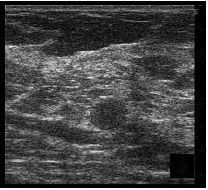

Se prepara la piel con anestesia local (lidocaína 1%) y para la punción ecodirigida del radiotrazador se utiliza una aguja espinal de calibre de 22 G. El radiotrazador nos lo aporta el Servicio de Medicina Nuclear y se trata del 99mtecnecio-coloide de albúmina (Nanocoll®, Amershan Health). La dosis es de 0,8-2 mCi diluidos en suero salino, lo que supone un volumen a inyectar de entre 0,3 a 1 ml. El radiotrazador se inyecta con control ecográfico en la periferia de la lesión con lo que, no sólo se localiza ésta, sino que se permite la migración del mismo hasta el ganglio centinela. Durante la inyección se comprueba cómo se produce un cambio de la ecogenicidad en el extremo de la aguja (fig. 1).

Fig. 1.--Nódulo hipoecoico visible en la ecografía (A). Durante la inyección del radiotrazador se produce un cambio de la ecogenicidad en el extremo de la aguja (B).